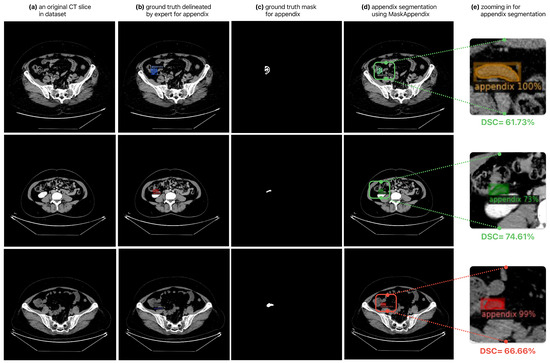

3.1. Results